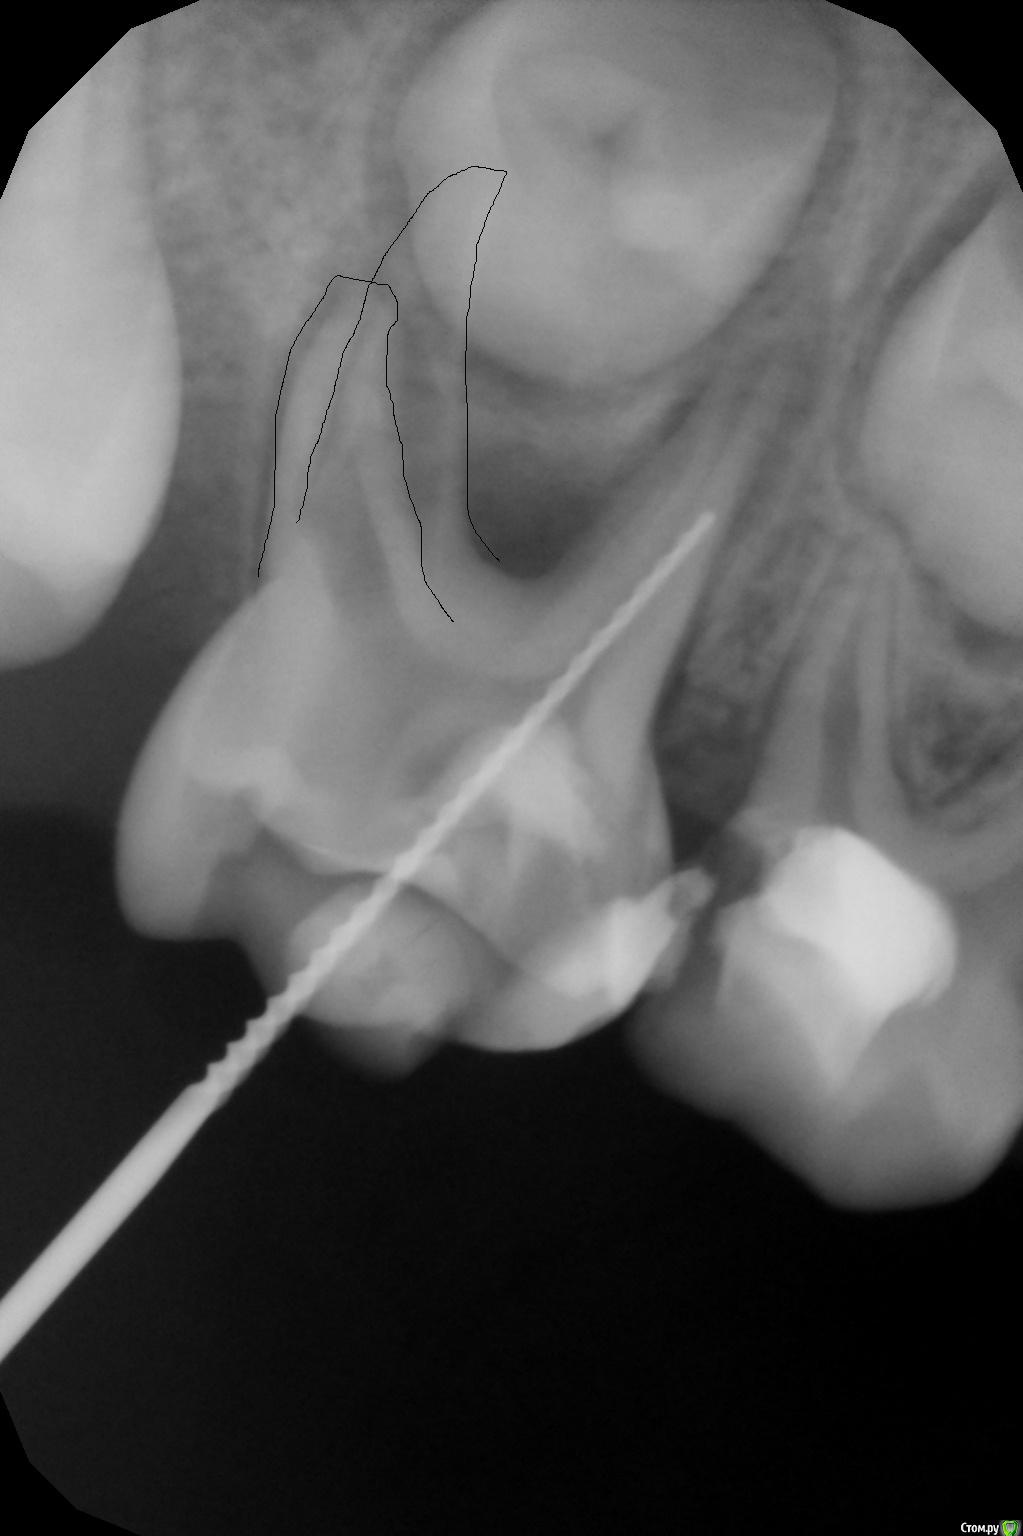

crown Опубликовано 31 мая, 2016 Поделиться Опубликовано 31 мая, 2016 5,5 лет, 75, ранее лечен по поводу кариеса, гигантская пломба, похоже на СИЦ, на десне с язычной стороны шишка), симптомы отсутствуют.Каналы про файлы 0.4 30, кровит нереально, особенно из дистальных, мед. обработка гипохлорит + перекись, оставил кальций на 2 недели. Сегодня свищ ушел, ничего не беспокоит, но дистальный язычный канал все равно кровит, остальные немного. Запломбировал метапексом вместе с кровью, назначил через пару дней. Почему кровит? И что делать с ним дальше? Удалять не хотят. Ссылка на комментарий

Джима Опубликовано 31 мая, 2016 Поделиться Опубликовано 31 мая, 2016 там же внутренняя резорпция обширная, в дистальных корнях. Надо было в дистальные не профайлами лезть, а вручную Н-файлами, и не "разрабатывать" ничего, а просто постараться выцарапать все грануляшки из каналов, не трогая сами стенки. возможно, что там уже дырки в стенках каналов были - тогда будет кровить, даже если в канале пусто. или вы дырки профайлом натёрли. или грануляции в каналах оставили. 2 Ссылка на комментарий

Kota Опубликовано 1 июня, 2016 Поделиться Опубликовано 1 июня, 2016 5,5 лет, 75, ранее лечен по поводу кариеса, гигантская пломба, похоже на СИЦ, на десне с язычной стороны шишка), симптомы отсутствуют.ИЛЬЯ_000.JPGКаналы про файлы 0.4 30, кровит нереально, особенно из дистальных, мед. обработка гипохлорит + перекись, оставил кальций на 2 недели. Сегодня свищ ушел, ничего не беспокоит, но дистальный язычный канал все равно кровит, остальные немного. Запломбировал метапексом вместе с кровью, назначил через пару дней. Почему кровит? И что делать с ним дальше? Удалять не хотят.ИЛЬЯ_я бы закрыла сейчас пломбой и ждала бы прорезывания 6 зуба. как только полностью прорежется шестерка- удалять и фиксатор места между 74 и 36. Ссылка на комментарий

crown Опубликовано 1 июня, 2016 Поделиться Опубликовано 1 июня, 2016 там же внутренняя резорпция обширная, в дистальных корнях. Надо было в дистальные не профайлами лезть, а вручную Н-файлами, и не "разрабатывать" ничего, а просто постараться выцарапать все грануляшки из каналов, не трогая сами стенки. возможно, что там уже дырки в стенках каналов были - тогда будет кровить, даже если в канале пусто. или вы дырки профайлом натёрли. или грануляции в каналах оставили.Думаете там 2 дистальных корня? Так то все верно, только резорбция в верхней трети корня, а дальше норм стеночки толстые, а кровит именно из апикальной части. Ссылка на комментарий